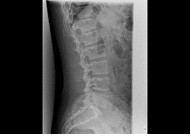

| 頸椎 | 腰椎 |